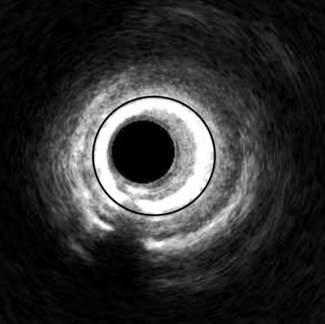

To address this challenge, a UCLA team of bioengineers, computer scientists, and physicians designed a stent to be implanted during an angioplasty and powered by the natural pulsing of blood through the artery. With each heartbeat, the artery expands and contracts, causing the stent’s magnetoelastic mesh to subtly change shape and generate magnetic signals. A small, flexible coil affixed to the skin above the artery with an adhesive picks up these magnetic changes, converting them into electrical signals that can then be analyzed remotely by physicians.

To test their prototype stent, the researchers implanted it in pig arteries using standard clinical catheters and real-time imaging guidance. A sensor coil was attached to the skin and electrical signals were recorded by a current preamplifier. The device successfully captured abnormal blood flow patterns with manually induced artery narrowing, and AI-assisted signal analysis confirmed the changes in real time.